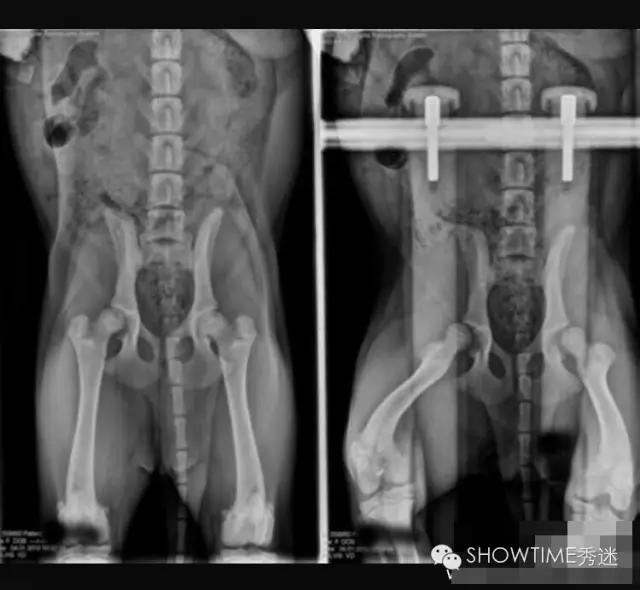

对于髋关节发育不良的判定,犬类骨科疾病种类很多,并非所有走路摇摆外八或者无力都是CHD。OFA组织是根据X光片来进行判断的,在犬只年满24月龄以后才会给出评判结果,24个月之前只做评估不做判定。因为犬在两岁前还在发育,股骨头和髋臼常会出现发育速度不一而产生髋关节发育不全的现象,这其中还要受到肌肉的影响。并且也有幼犬时期髋关节发育正常,而后随着成长过程发生严重变化,进而产生CHD症状,因此判定:只有在24月龄之后才可以做出。这是在美国和全世界至今应用最为广泛的方法,也是美国繁殖者在繁殖中的主要依托。

在髋关节发育不良的诊断中有一个最为重要的因素,就是X光片的拍摄要求。在国内很多医院因此而产生的误诊不胜枚举。